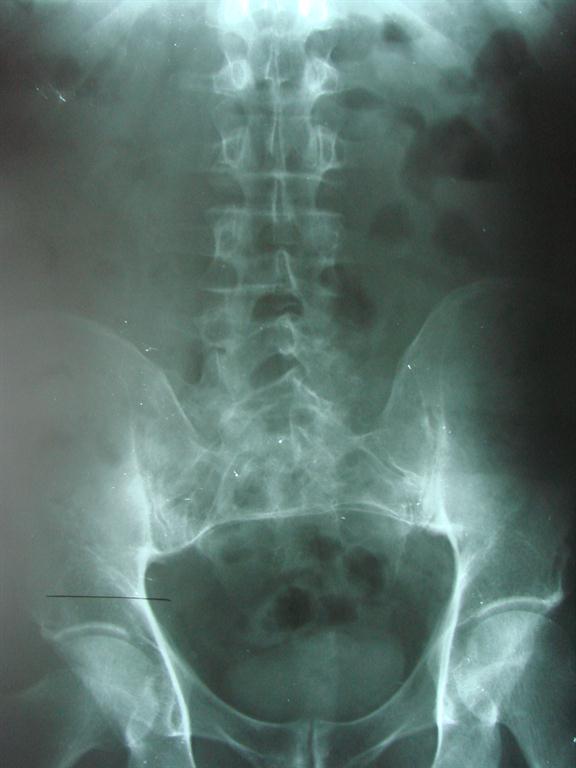

A thorough, clinical examination that may include imaging is important to your short leg diagnosis and management.